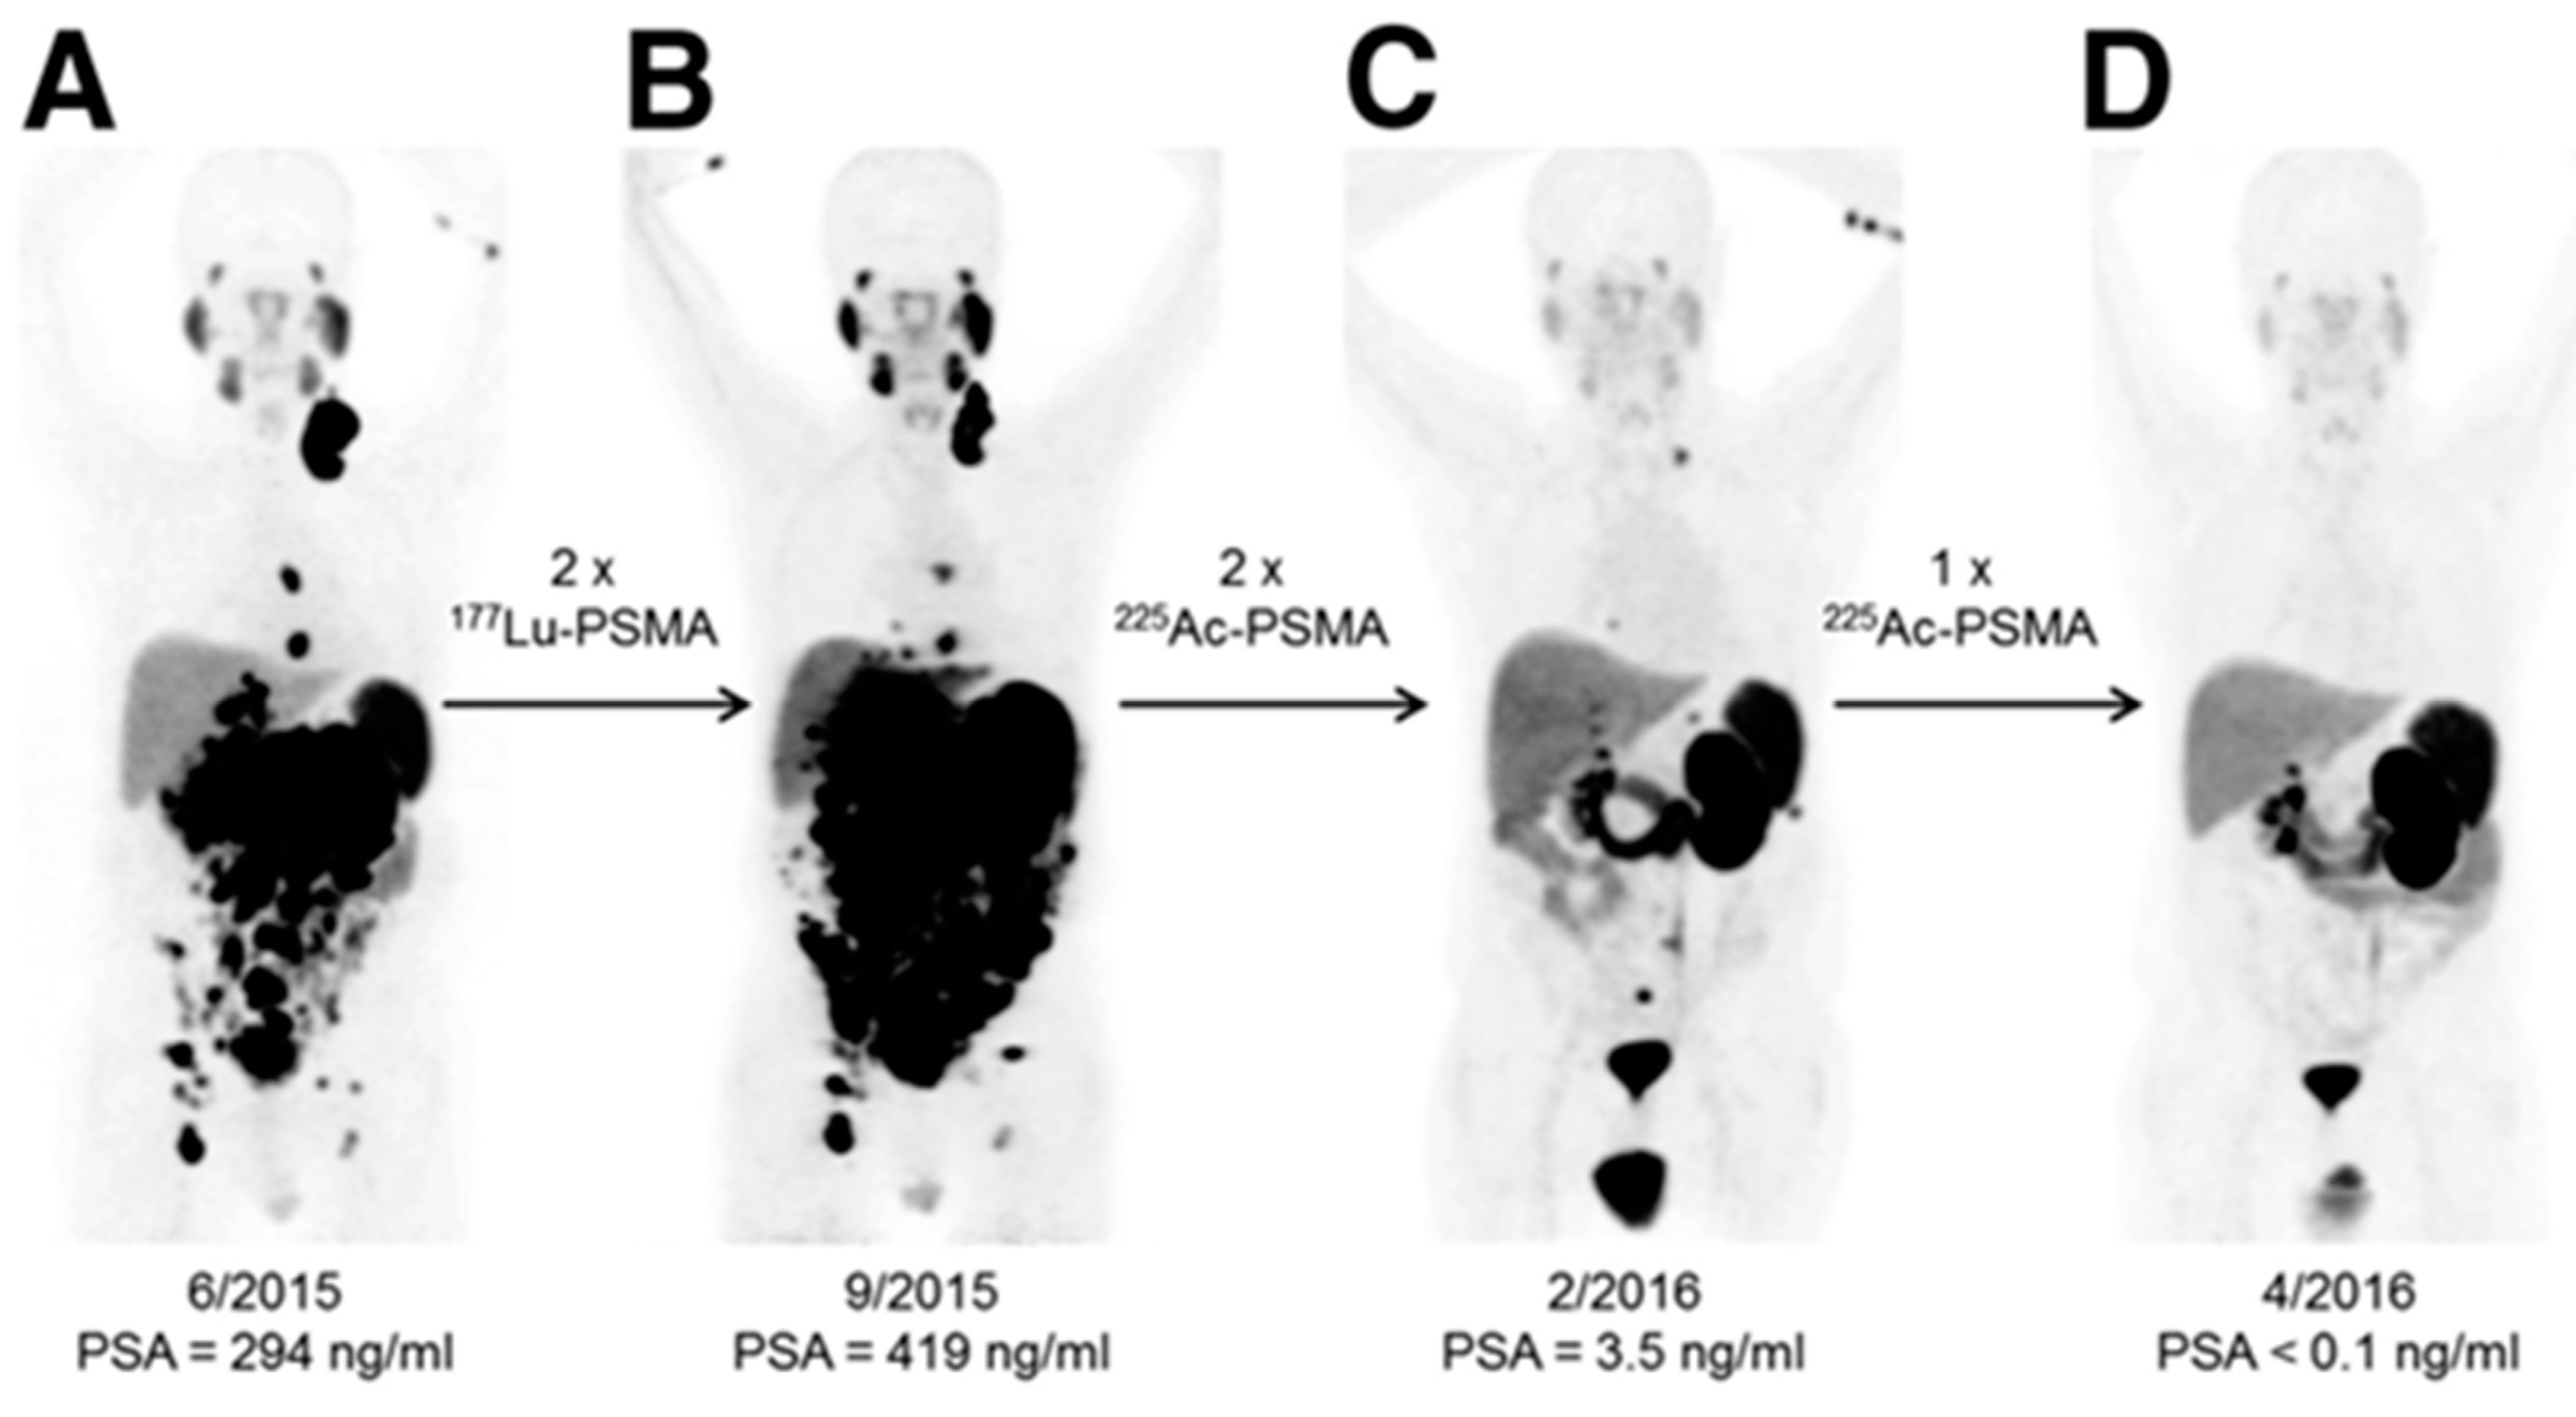

Alpha (α)-particles have a linear energy transfer of 100 keV/µm compared to the 0.2 keV/µm of β-particles in tissue. The higher LET means a larger portion of the total radiation dose is delivered over an equal pathlength. Alpha (α)-particles can deliver up to 1000× more dose to cells than β-particles, even with the same number of radioactive decays. This high energy allows for double rather than single-strand DNA breaks, leading to increased cell death. Cancer cells can adapt to single-stranded DNA breaks and survive, but struggle when double-strand breaks occur. An incredible example of this occurred when β-resistance was overcome with α-particle therapy with Ac-225-PSMA [49]. As shown in Figure 5, Lu-177-PSMA was unable to debulk tumors or decrease PSA levels in this patient, but repeated doses of Ac-225-PSMA led to complete tumor eradication and a return to normal levels of PSA. Improvements in neuroendocrine cancer therapy are also seen when an α-particle emitter is used instead of β-radiation [50,51].

Figure 5.

Alpha (α)-particle therapy overcomes β-resistant cancer. This imaging was performed using Ga-68-PSMA-11 PET/CT scanning. Kratochwil, C. et al. [49] reports, “In comparison to initial tumor spread (A), restaging after 2 cycles of β-emitting 177Lu-PSMA-617 presented progression (B). In contrast, restaging after second (C) and third (D) cycles of α-emitting 225Ac-PSMA-617 presented impressive response.” This research was originally published in The Journal of Nuclear Medicine [49].